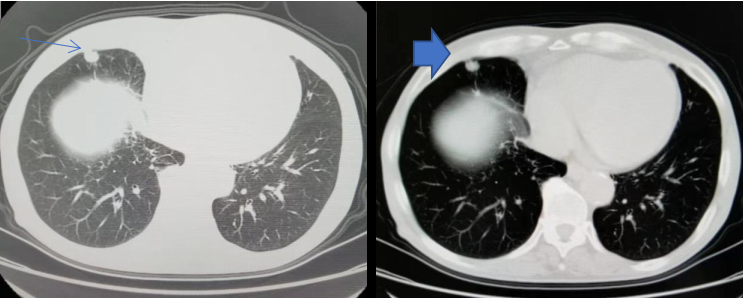

2022年1月胸部CT(图5):

右肺中叶切除术后,未见明显肿瘤复发征像;

右侧少量胸腔积液较前吸收;

右肺慢性炎症较前相仿;

双肺少许感染已吸收;

左肺下叶间裂处小结节同前,建议随访;

脂肪肝,肝脏小囊肿;

胃癌术后改变。

图5.胸部CT影像